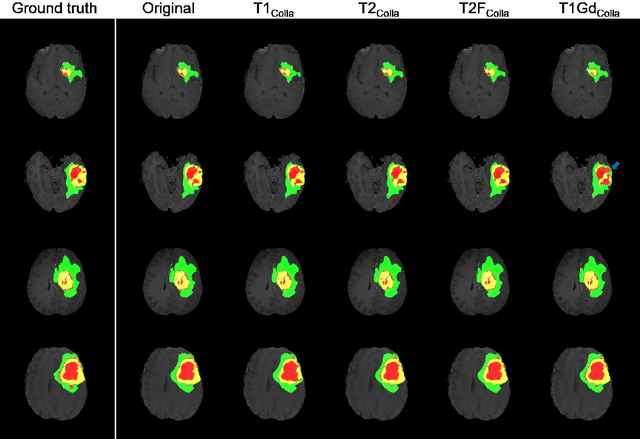

Abstract:Thanks to the recent success of generative adversarial network (GAN) for image synthesis, there are many exciting GAN approaches that successfully synthesize MR image contrast from other images with different contrasts. These approaches are potentially important for image imputation problems, where complete set of data is often difficult to obtain and image synthesis is one of the key solutions for handling the missing data problem. Unfortunately, the lack of the scalability of the existing GAN-based image translation approaches poses a fundamental challenge to understand the nature of the MR contrast imputation problem: which contrast does matter? Here, we present a systematic approach using Collaborative Generative Adversarial Networks (CollaGAN), which enable the learning of the joint image manifold of multiple MR contrasts to investigate which contrasts are essential. Our experimental results showed that the exogenous contrast from contrast agents is not replaceable, but other endogenous contrast such as T1, T2, etc can be synthesized from other contrast. These findings may give important guidance to the acquisition protocol design for MR in real clinical environment.

Abstract:In many applications requiring multiple inputs to obtain a desired output, if any of the input data is missing, it often introduces large amounts of bias. Although many techniques have been developed for imputing missing data, the image imputation is still difficult due to complicated nature of natural images. To address this problem, here we proposed a novel framework for missing image data imputation, called Collaborative Generative Adversarial Network (CollaGAN). CollaGAN converts an image imputation problem to a multi-domain images-to-image translation task so that a single generator and discriminator network can successfully estimate the missing data using the remaining clean data set. We demonstrate that CollaGAN produces the images with a higher visual quality compared to the existing competing approaches in various image imputation tasks.